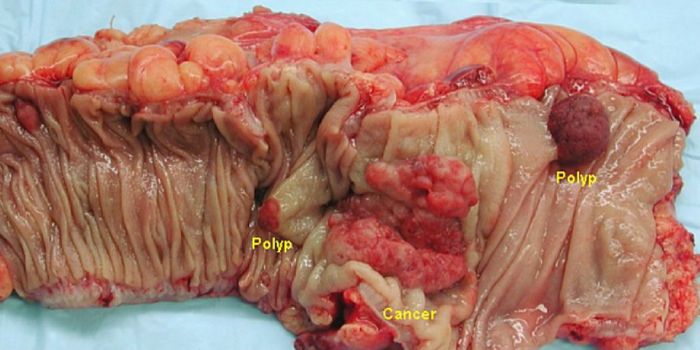

APR 13, 2017CancerThe onset of colon cancer may be tied to antibiotic use, reported scientists. The importance of the microbiome has only ...